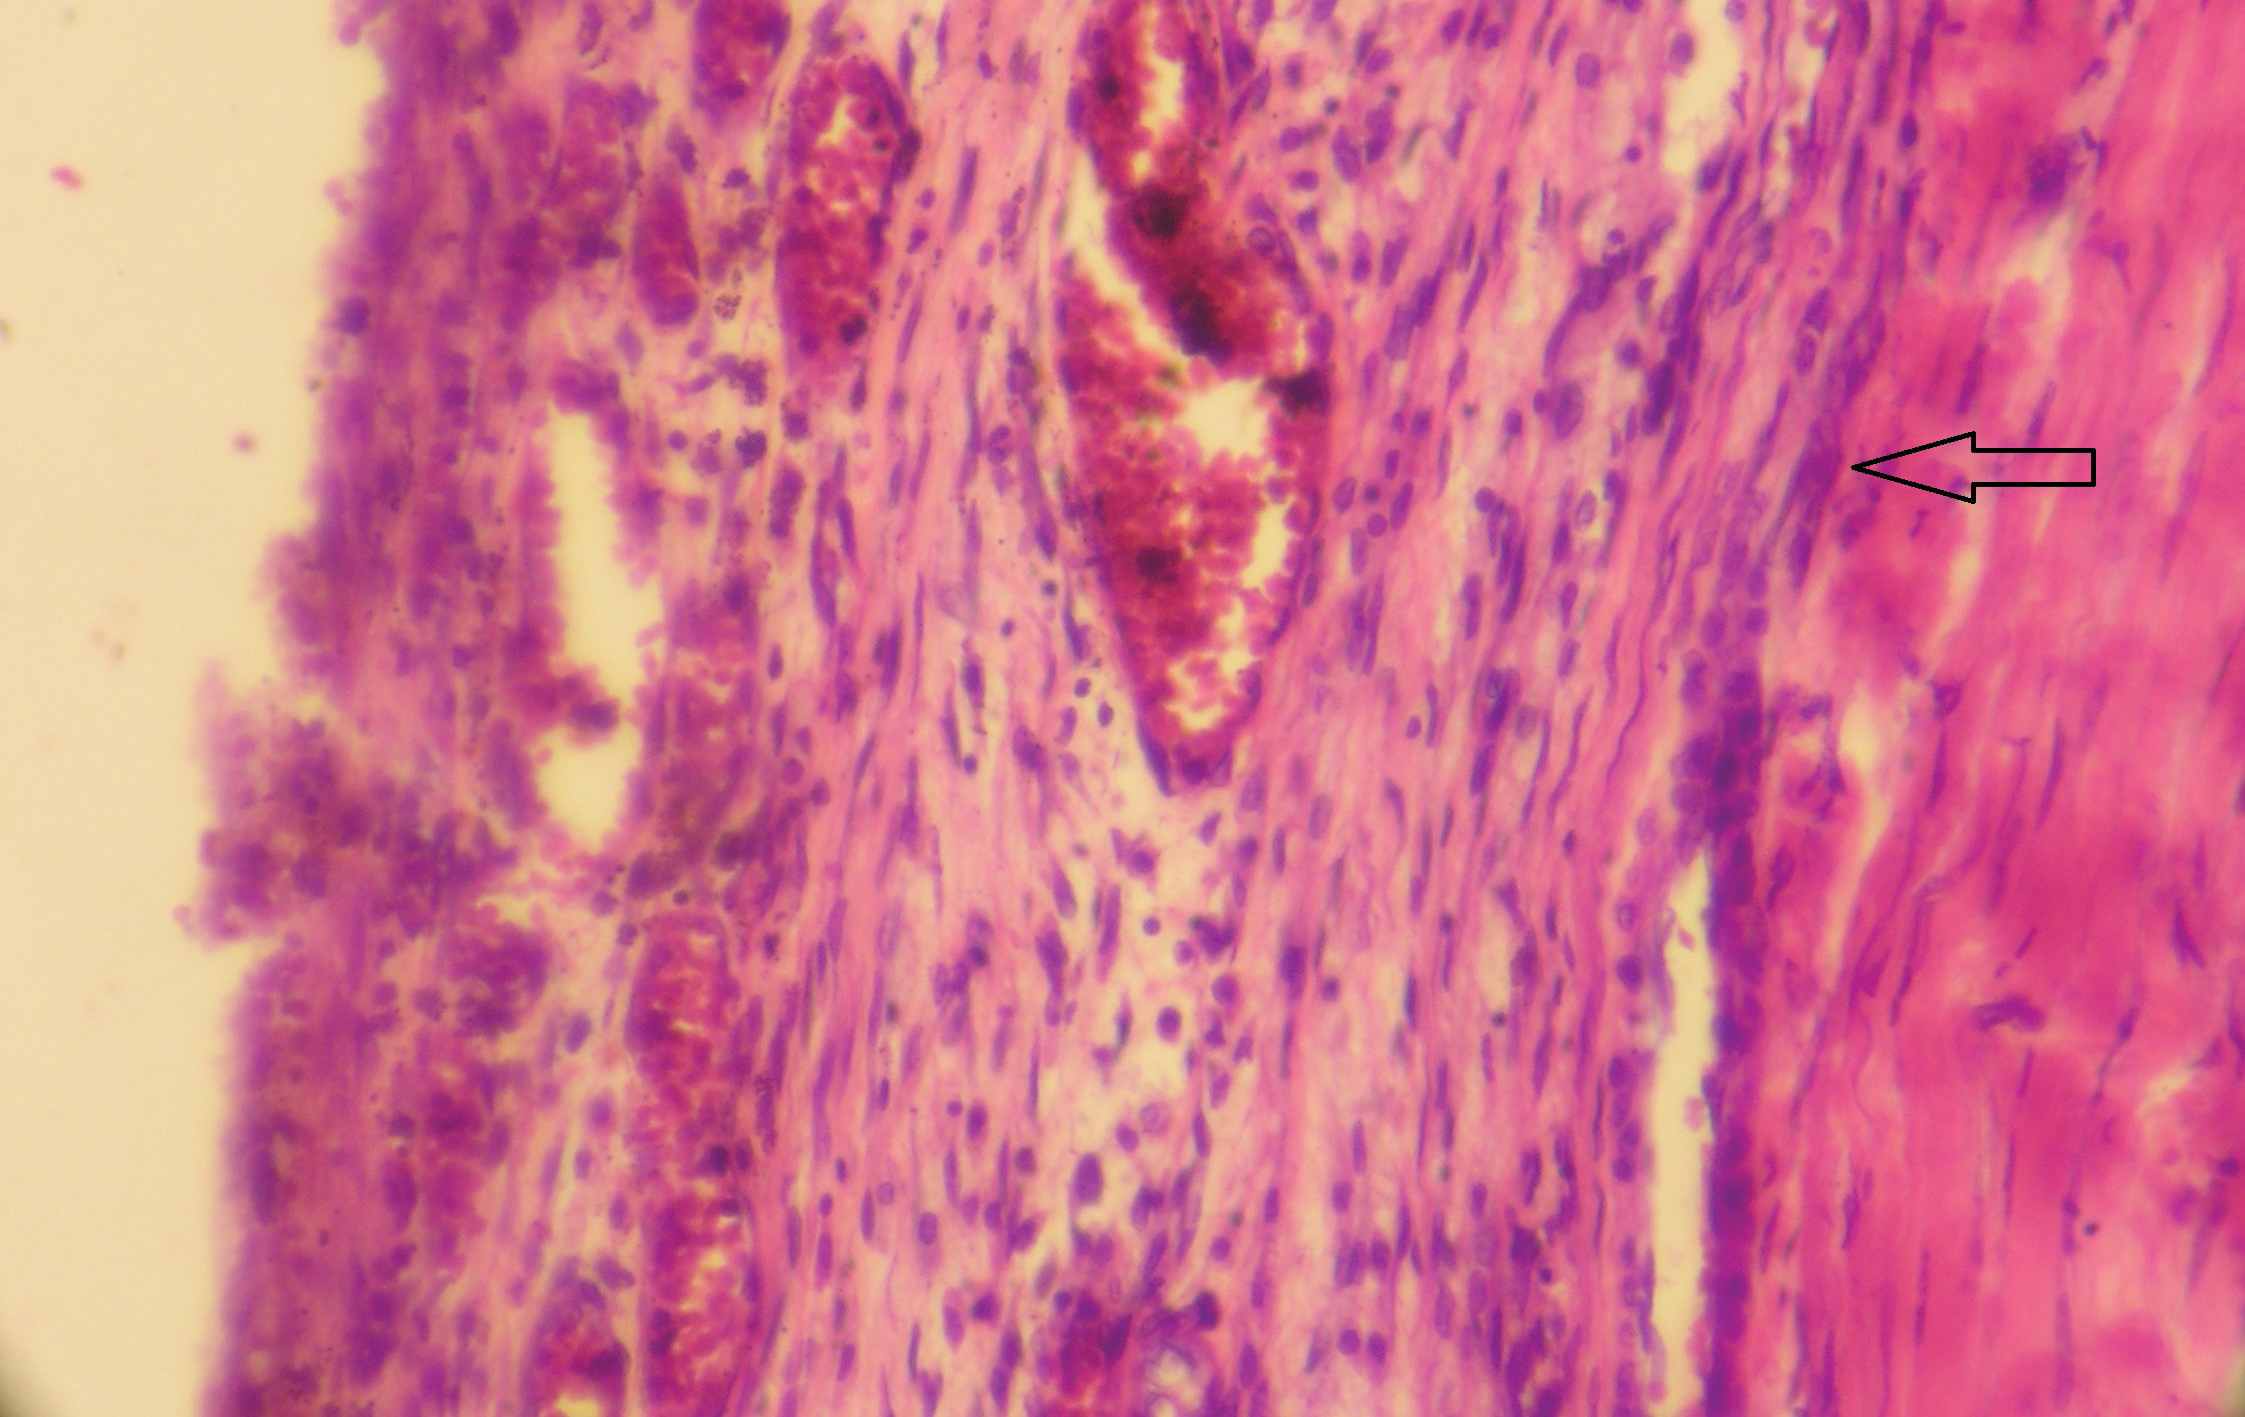

В зависимости от наличия и выраженности организации все СГ подразделяются на три основных класса: неинкапсулированные, инкапсулированные и стабильно организованные. Неинкапсулированные СГ характеризуются макроскопическим наличием в субдуральном пространстве жидкой крови или ее свертков без признаков инкапсуляции (рисунок 1). С момента своего образования все СГ являются неинкапсулированными, первые проявления инкапсуляции начинают регистрироваться спустя 3 суток существования СГ, а к 10 суткам все СГ являются инкапсулированными.

Рисунок 1. Неинкапсулированная СГ. Содержимое гематомы не содержит фибрина и не спаяно с ТМО. Окраска гематоксилином и эозином. 64х.